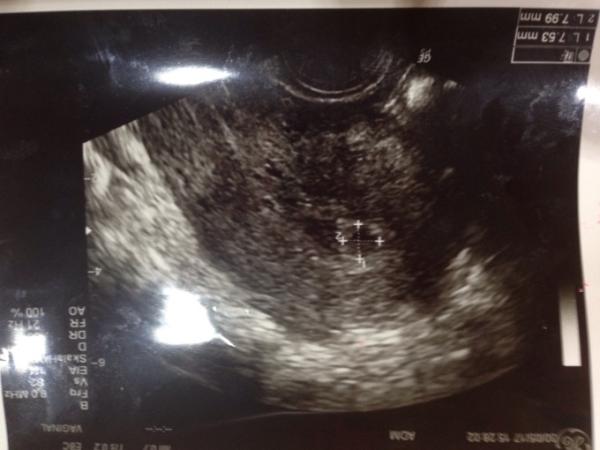

hallo bin verzweifelt nach meine 2 kryo mit einem 8 zeller bin ich ca. in der 5 ssw hatte vor 2 tagen einmalig einen blutstoss dann nix mehr war gestern beim frauenarzt der sagte es sei wahrscheinlich blut in der gebärmutter aber dottersack ist auch da bissi klein aber er ist da gebärmutter schleimhaut ist 1,2 cm und dottersack bei 7,5mm mal 7,9mm was sagt ihr dazu habe ich noch zu hoffen lg

Bild zu blut in der gebärmutter - Schwanger - wer noch? Rund um die Schwangerschaft